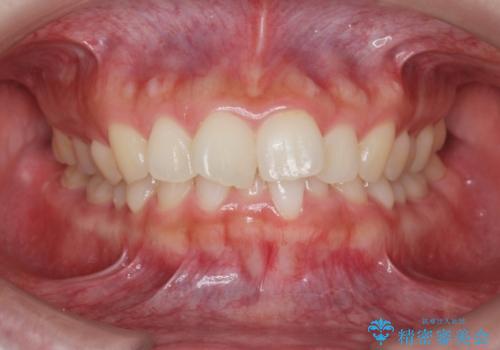

![[ インビザライン矯正 ] マウスピース矯正で治す、前歯のガタつきの症例 治療前](https://seimitsushinbi.jp/wp/wp-content/uploads/2022/02/324533f54aaa29eca08b0a9fdd3af7e2-500x350.jpg?v=1644473292)

![[ インビザライン矯正 ] マウスピース矯正で治す、前歯のガタつきの症例 治療後](https://seimitsushinbi.jp/wp/wp-content/uploads/2022/02/IMG_1698-500x350.jpg?v=1644473356)